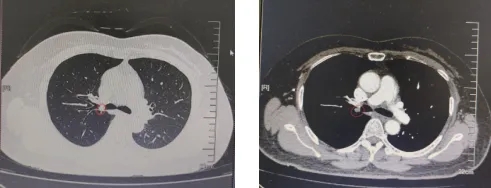

胸部增强CT图像显示:右肺上叶支气管开口肿块,大小约1厘米

入院后完善的胸部增强CT与支气管镜检查进一步明确:肿块为带蒂光滑团块,且从支气管外侧壁可窥见完整右上叶支气管,具备支气管镜下切除的条件。